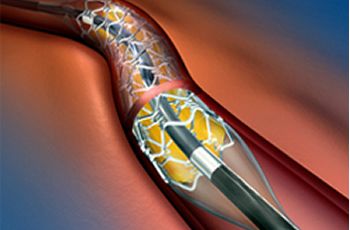

Angioplastia coronaria

Angioplastia coronaria más colocación de stent

Valvuloplastia hemodinámica